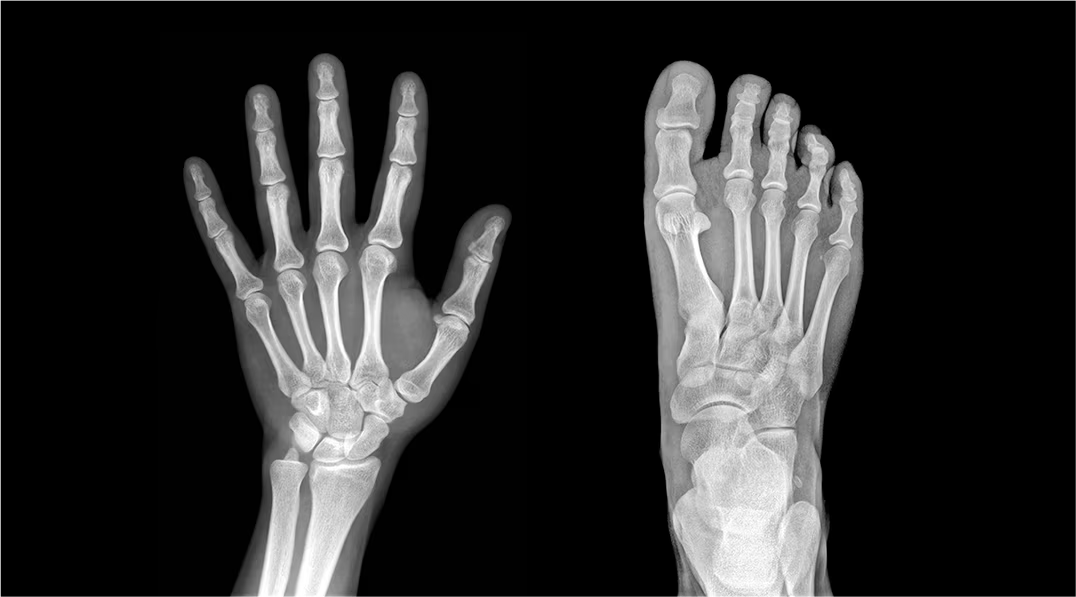

What is x-ray imaging used for?

detecting broken bones

finding breast tumors

screening for osteoporosis

What are the light areas in x-ray imaging?

dense structures

What are the dark areas in x-ray imaging?

hollow air-containing organs

What are the drawbacks of x-ray imaging?

radiation exposure

2D images